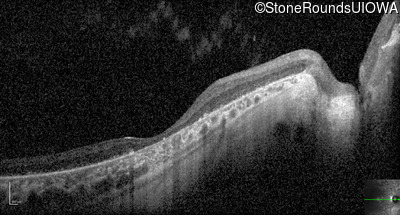

Optical Coherence Tomography - Right - 5/180

Exemplar / OCT Stack

OCT Stack